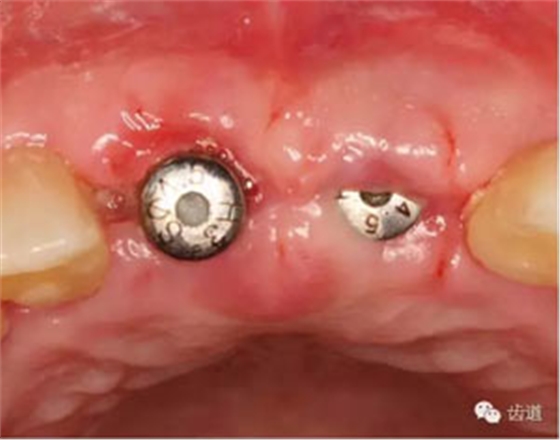

合面觀

袖口形態(tài)